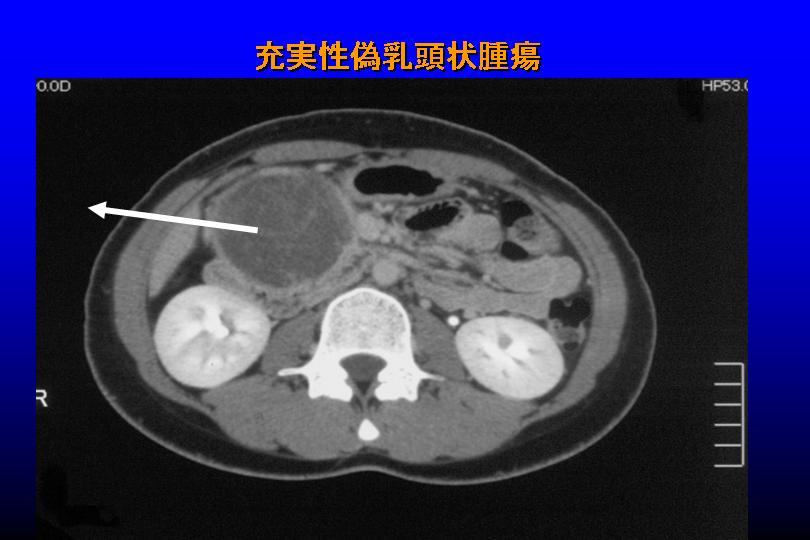

B子さんの場合は、膵臓の外に突出する格好で20センチ以上もの腫瘍ができた。充実性偽乳頭状腫瘍(写真)と診断、その大きさに執刀した田中教授も驚いたが、やはり腹腔鏡下手術を行い腫瘍部分だけを核出術で取り除くことができた。

〈写真説明〉いずれもCT画像による。矢印部分(丸く黒い部分)を切除した。